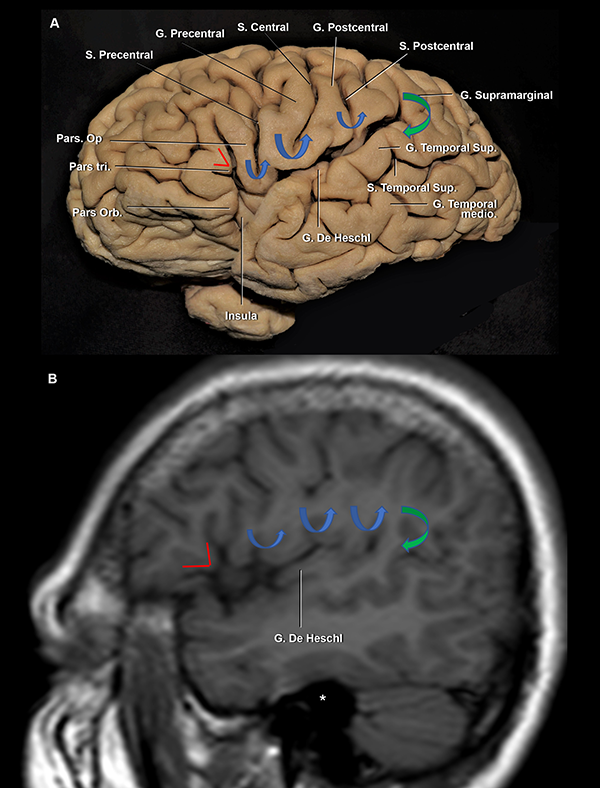

Figura 5: A. Vista lateral de un hemisferio cerebral izquierdo. B. RMN, secuencia T1, corte sagital. La pars triangularis tiene forma de “V” (líneas rojas). Luego, encontramos 3 giro con forma de “U” (flechas azules), de anterior a posterior: 1) pars opercularis; 2) giro subcentral; y 3) la conexión entre los giros postcentral y supramarginal. Finalmente, la flecha verde marca la conexión con forma de “C” entre los giros supramarginal y temporal superior. Se observa al giro de Heschl enfrentado al postcentral. Ambos se encuentran en el mismo plano coronal que el CAE. Asterisco: proyección medial del CAE. S: surco; G: giro; Sup: superior; inf: inferior.

El techo de la fisura silviana está conformado por los lóbulos frontal y parietal. La palabra operculum proviene del latín y significa “cortina”:21 los lóbulos frontal, parietal y temporal cubren armónicamente a la cisterna silviana e ínsula (Figura 5A).

El giro frontal inferior se divide por los ramos superficiales de la FS, de anterior a posterior, en la pars orbitalis, la triangularis y la opercularis (Figura 3 y 5A).

La pars orbitalis se continua basalmente con los giros orbitarios lateral y posterior. Es el área más prominente del giro frontal inferior (Figura 5A y 9A)22 y se relaciona superficialmente con el keyhole (agujero de trépano llave) del abordaje pterional.

La pars triangularis, que posee una forma de “V”,22,23 suele albergar un ramo originado del surco frontal inferior y cubre al ápex insular. Por otro lado, la pars opercularis, que tiene forma de “U”,22 alberga un ramo originado del surco precentral, o en su defecto, al extremo inferior del surco precentral (Figura 3 y 5). La pars opercularis, se recuesta superficialmente sobre el giro corto posterior de la ínsula (Figura 4A). Más aún, la rodilla de la cápsula interna y el foramen de Monro se ubican en la profundidad de dicho giro corto (Figura 12B). Finalmente, el área de Broca del lenguaje, se compone de la pars triangularis y opercularis del hemisferio dominante.22

El lóbulo central se localiza posterior a la pars opercularis y se compone de los giros pre y postcentral.18,22 El puente neural que conecta dichos giros en el extremo inferior del surco central es el giro subcentral, también denominado pli de passage frontoparietal inferior de Broca u opérculo rolándico (Figura 4A y 5A).22,23 El giro precentral se recuesta superficialmente sobre el tercio medio de la corteza insular y el cuerpo de los ventrículos laterales. El surco central corre en una dirección paralela al surco central de la ínsula. Está reportado en la literatura que hasta en el 84% de los casos, el surco no se extiende hasta contactar la FS, en consonancia con nuestros hallazgos.12,18 El giro postcentral se ubica superficial al tercio posterior de la ínsula (Figura 4A y B).

La parte más posterior del techo de la fisura silviana la conforma el giro supramarginal, que alberga al ramo terminal ascendente de la fisura silviana. El opérculo supramarginal envuelve al punto silviano posterior, conectando a los giros supramarginal con el temporal superior (Figura 3 y 5). En la profundidad del margen más anterior del giro supramarginal es encontrado el punto insular posterior, que marca a su vez el extremo posterior del lóbulo insular (Figura 6). Asimismo, el extremo posteromedial del giro de Heschl se localiza justo posterior al punto insular posterior (Figura 12B).

El plano temporal está compuesto por dos o tres giros transversos. Es un área de forma triangular cuyo ápex apunta hacia el atrio ventricular. El giro de Heschl y la parte posterior del giro temporal superior constituyen el área auditiva primaria (Figura 6A, 10A y B).22 En su extremo anterolateral, el giro de Heschl se encuentra en el mismo plano coronal que el giro postcentral. Además, se evidenció que el giro de Heschl a su vez se encuentra en el mismo plano que el conducto auditivo externo (CAE) (Figura 5). En el plano coronal, tiene una orientación horizontal, haciendo que la disección de la fisura en esta área sea más dificultosa.